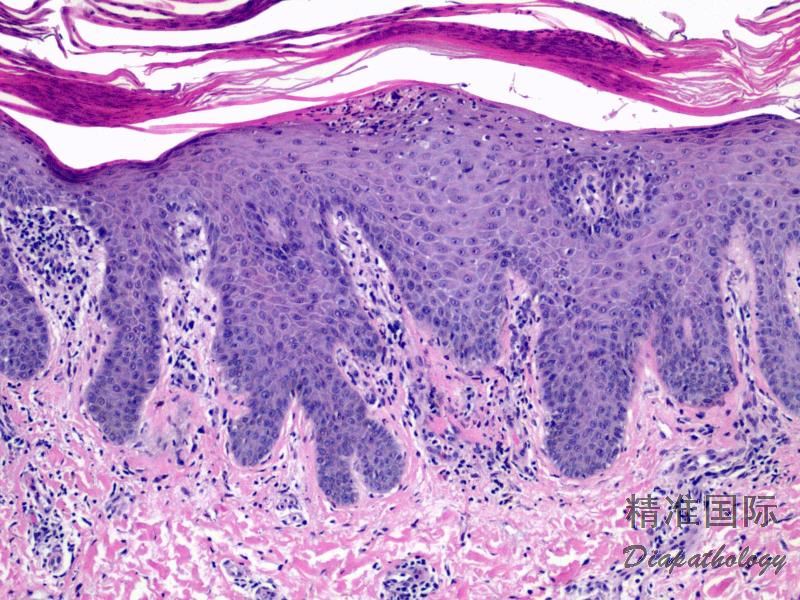

银屑病通常根据临床表现即可诊断,无需活检或辅助检查,临床表现典型时可行组织学检查。组织学改变:充分发展的斑块表现为角化不全伴中性粒细胞浸润、上皮脚明显规则性延长、颗粒层减少、乳头层上方表皮变薄、真皮乳头内血管扩张、迂曲及真皮浅层血管周围淋巴细胞为主的炎症细胞浸润。急性、点滴型或脓疱型皮损表现为中性粒细胞性海绵水肿、海绵水肿性脓疱(Kogoj 微脓疡,指表皮内中性粒细胞的聚集,可位于基底层、棘细胞层或颗粒层)及 Munro 微脓疡(指中性粒细胞在角质层内聚集)。中性粒绑胞在表皮内聚集很明显,但在真皮内并不多见。嗜酸性粒细胞在银屑病中通常不多见。